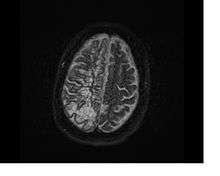

Perivascular spaces are extremely small and can usually only be seen on MRI images when dilated. While many normal brains will show a few dilated spaces, an increase in these has been shown to correlate with the incidence of several neurodegenerative diseases, making the spaces a popular topic of research.[1]

Perivascular spaces are most commonly located in the basal ganglia, thalamus, midbrain, cerebellum, hippocampus, insular cortex, the white matter of the cerebrum, and along the optic tract.[6] The ideal method used to visualize perivascular spaces is T2-weighted MRI. The MR images of other neurological disorders can be similar to those of the dilated spaces. These disorders are: [4]

Perivascular spaces are distinguished on an MRI by several key features. The spaces appear as distinct round or oval entities with a signal intensity visually equivalent to that of cerebrospinal fluid in the subarachnoid space.[4][7][8] In addition, a perivascular space has no mass effect and is located along the blood vessel around which it forms.[7]